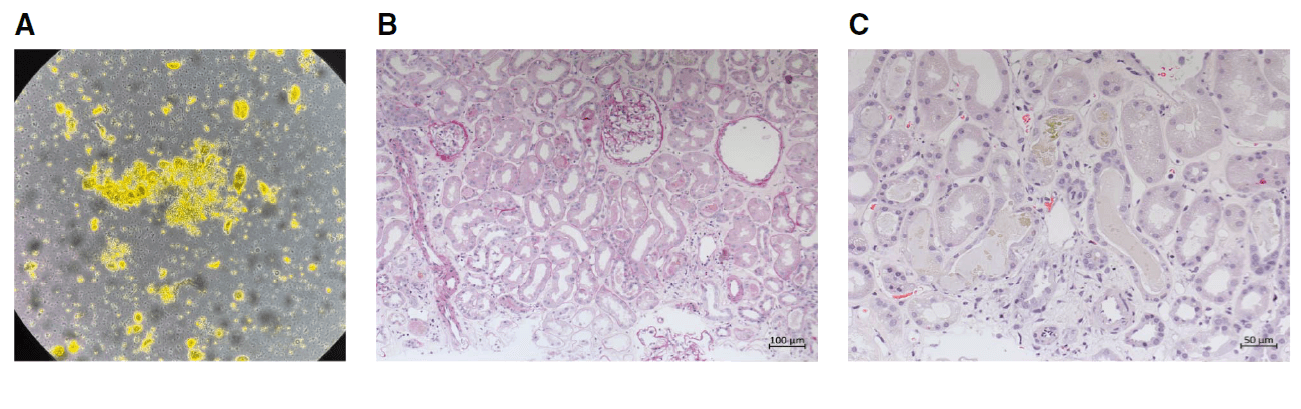

**Figura 1.** Achados urinários e histológicos da biópsia renal. (A) O sedimento urinário mostra células epiteliais tubulares, cilindros granulares corados por bile e cristais de leucina. (B) Os túbulos renais apresentam células epiteliais achatadas e perda da borda em escova (NTA). (C) Os túbulos exibem cilindros amarelo-esverdeados corados por bile (H&E).

O sedimento urinário revelou cilindro biliares, cristais de leucina e células tubulares — achados que direcionam o raciocínio para lesão tubular por pigmentos.

Foi realizado biópsia confirmando existência de necrose tubular aguda com cilindros biliares, compatível com Nefropatia Colêmica.